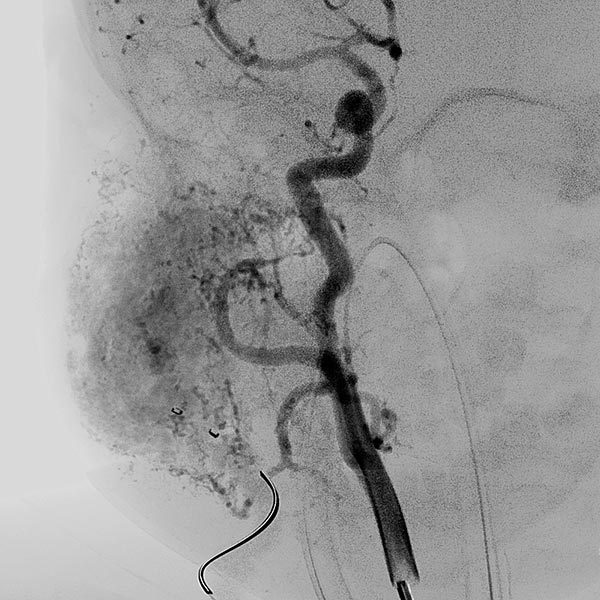

Das Mädchen ist jetzt 24 Monate alt, die Raumforderung hat sich nicht zurückgebildet. Sie ist deutlich sichtbar und bereitet der Patientin klaren Druckschmerz. Die MIP einer dynamischen, kontrastmittelunterstützten MR-Angiographie zeigt die starke Anreicherung des Hämangioms, das immer noch ausgedehnt ist. Die hauptsächliche venöse Drainage läuft über die Vena jugularis externa, im proximalen Bereich zeigt sich hier eine massive Stenose des Abstroms.

Aufgrund der fehlenden Rückbildung, wahrscheinlich auch durch die massive Stenose des venösen Abstroms, fällt der Entschluss zur Embolisation des Hämangioms im 24. Lebensmonat zur Induktion einer Regression. Zunächst wird dazu retrograd von transvenös der venöse Abstrom (Vena jugularis externa rechts) kanüliert.

Anschließend wird dann ein kleiner Ballonkatheter eingebracht, der den venösen Abstrom vor einer Embolisation blocken soll und damit eine Embolisatverschleppung vermeiden soll.